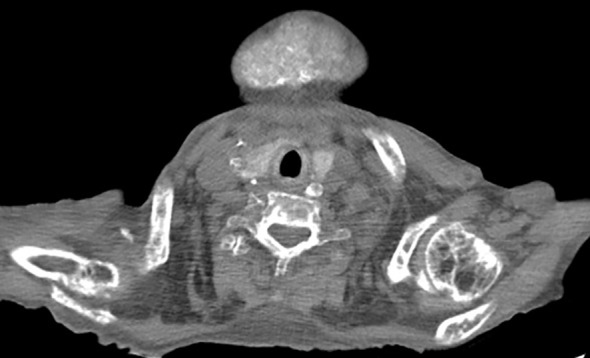

三期甲状旁腺功能亢进(THPT)是不受控制的继发性甲状旁腺功能亢进的严重并发症,通常与晚期慢性肾脏疾病(CKD)相关。我们报告了一名洪都拉斯患者的病例,她长期患有继发于严重子痫前期的CKD病史,由于经济拮据和COVID-19大流行,她在停止治疗后患上了THPT。患者表现出严重的颌面畸形、功能限制和广泛的骨骼异常。尽管最初使用了paricalcitol和alfacalcidol等药物进行治疗,但由于缺乏适当的治疗方法和计划中的甲状旁腺切除术的推迟,使她的病情恶化。该病例强调了早期诊断和及时干预的重要性,特别是在资源有限的情况下,强调了发展中国家迫切需要肾脏移植项目和改进预防策略。

Tertiary hyperparathyroidism (THPT) is a severe complication of uncontrolled secondary hyperparathyroidism, typically associated with advanced-stage chronic kidney disease (CKD). We present the case of a Honduran patient with a long-standing history of CKD secondary to severe preeclampsia, who developed THPT following the discontinuation of her treatment due to financial constraints and the COVID-19 pandemic. The patient exhibited severe maxillofacial deformities, functional limitations, and widespread skeletal abnormalities. Despite initial management with medications such as paricalcitol and alfacalcidol, the lack of access to appropriate therapies and the postponement of a planned parathyroidectomy worsened her condition. This case highlights the importance of early diagnosis and timely intervention, particularly in resource-limited settings, emphasizing the urgent need for kidney transplant programs and improved preventive strategies in developing countries.